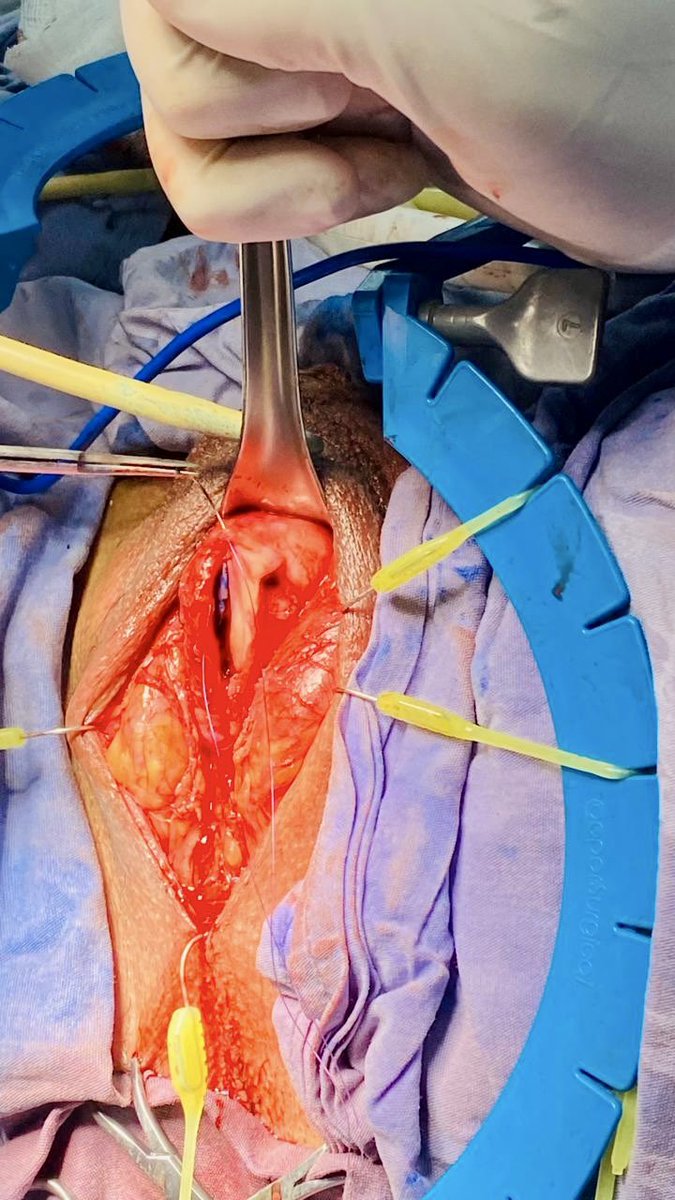

36a con estrechez uretral post instrumentación, con qmax 2.2 ml/s y 90% OR. Sin UTI previa, por la longitud decidí someterlo a plastia de uretra técnica Dr Sanjay Kulkarni con BMG. Con una disección de planos muy sencilla debido a no tener antecedente de tratamiento.

36a con estrechez uretral post instrumentación, con qmax 2.2 ml/s y 90% OR. Sin UTI previa, por la longitud decidí someterlo a plastia de uretra técnica <a href="/sanjaybkulkarni/">Dr Sanjay Kulkarni</a> con BMG. Con una disección de planos muy sencilla debido a no tener antecedente de tratamiento.